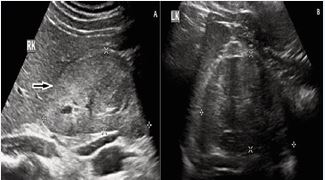

We present a case of 22-year-old overweight, female student who was found to have high blood pressure during routine checkup. She did not have any symptoms prior to the hospital visit. There was no family history of hypertension or familial dyslipidemia. Her maximal recorded blood pressure was 190/110 mmHg in both the arms. All peripheral pulses were palpable with no radio radial or radio-femoral delay. The initial clinical exam showed an overweight (BMI- 24.5 kg/m2) female patient with normal cardiovascular, respiratory, and central nervous system examinations and no detectable heart or vascular (including abdominal) bruits. There were no features of hypo- or hyperthyroidism and Cushing’s syndrome. Routine blood investigations including urea, creatinine were normal. Serum electrolyte showed mild hypokalemia (3.1 mmol/L). No changes were found concerning the plasmatic and urinary cortisol and thyroid hormones’ dosages. The urine analysis revealed no signs of proteins, red cells or cellular elements. We evaluated 17 hydroxyprogesterone, testosterone, luteinizing hormone, follicle-stimulating hormone, and prolactin in order to eliminate the possibility of an 11-hydroxylase deficiency (known to associate elevated BP and hypokalemia tendency). Also, the progesterone was measured on the 22nd day, in order to document the ovulation and plasma free metanephrine. The results of the above-mentioned tests were not relevant for any endocrine possible cause of hypertension in this particular case (pheochromocytoma, Cushing disease,11 hydroxylase deficiency). Moreover, the patient was not using oral contraceptives.Additionally, we attempted to dismiss the possibility of a reno parenchymal hypertension. Therefore, we performed an abdominal ultrasound that did not show any renal or adrenal masses, but there was major size difference between the two kidneys (left kidney 105 mm and tight kidney 85 mm) with normal cortico-medullary differentiation possibly suggesting renal artery stenosis) (Figure 1).

Figure 1: Ultrasonography of abdomen revealed small right kidney

Her chest X-ray and ECG were normal. During the echocardiography investigation, a slight hypertrophy of the ventricular walls was described, without any impact on the overall and segmented heart function and no hemodynamically significant valvulopathy.We started her on standard anti-hypertensive medications with combination of calcium channel blocker and angiotensin receptor blocker and did further investigations. As renal artery stenosis was suspected from clinical examination, renal Doppler was performed, which did not reveal any renal artery stenosis. Because of low sensitivity of the renal Doppler examination, arterial stenosis was not ruled out. Since clinical examination and different kidney sizes were in favor of renal artery stenosis, we decided to go for CT renal angiography which revealed multifocal renal FMD in right renal artery with angiographic appearance of strings of beads (Figure 2). Left renal artery was normal.